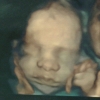

Elbetteki hamileliğin ilk haftaları sizin için oldukça heyecan verici. Önce bebeğin kesesini görmek, ardından ilk kalp atışlarını duymak, sonraki haftalarda hareketleri vs. bebeğiniz adeta her doktor kontrolünde size ayrı bir sürpriz yaşatıyor gibi. Peki bu sürprizi bir adım daha yukarı taşımaya ne dersiniz? Bahçeci Tüp Bebek Merkezi Kadın Hastalıkları ve Doğum Uzmanı Op. Dr. Burçak Erzik; Tıbbi görüntüleme teknolojileri büyük bir hızla ilerliyor. HD Live Ultrason anne karnındaki bebeğin görüntülenmesinde değişik ışıklandırma ve renklendirme teknikleri kullanıyor ve böylece gerçeğe en yakın görüntülerin elde edilmesine olanak sağlıyor. Bütün bu teknolojik imkânları kullanmanın en keyifli yanı anne adaylarına henüz bebekleri doğmadan gerçeğe en yakın görüntüyü sunuyor olmamız. Anne karnındaki bebeğinizin gülüşünü, somurtuşunu, uyuyuşunu tıpkı TV izler gibi izleyebiliyorsunuz" dedi.

Bebeğin gelişimini takip etmek adına her ay gidilen doktor kontrolleri, ultrason takipleri çok önemli. Ancak artık ultrason ebeveynler için sadece bebeklerinin gelişimini tıbben takip ettikleri an olmaktan çıktı. Henüz anne karnındaki bebekleriyle ilk kez tanıştıkları, sonraki doktor kontrollerinde de buluşmaya devam ettikleri anlar oldu. Üstelik ultrason teknolojisi o kadar gelişti ki artık bebeğinizi size yüksek çözünürlükle gerçeğine en yakın şekilde gösterir oldu. Op. Dr. Burçak Erzik; "HD 4 Boyutlu ultrason ile aylık rutin kontroller aileler için daha da eğlenceli olmaya başladı. Bebeğinin ilk mimiklerini gören anne ve babanın heyecanı, mutluluğu gebeliğin daha olumlu geçmesini sağlıyor. Öte yandan şahit olduğumuz ilginç anlar da yaşanmıyor değil. Bazen bebeklerin en keyifli anlarına denk geliyoruz şekilden şekle giren oluyor; düşünür gibi ellerini kafasına koyuyor ya da kaşlarını çatıyor" dedi.

Yüksek çözünürlüklü 4 boyutlu ultrasonun erken tanı ve tedavide de önemli bir adım olarak değerlendirilmesi gerektiğini belirten Op. Dr. Erzik; "üçüncü aydan itibaren cinsiyeti öğrenme ve renkli görüntülerini kayıt altına alma fırsatlarının yanı sıra, çok erken dönemde yarık damak, yarık dudak, eksik parmak, beyin ve omurilikten kaynaklanan rahatsızlıkların, kalp ve damar, böbrek, bağırsak ve karın duvarı anormalliklerinin erken tanısı koyabilmekteyiz" dedi.

HD Live 4D ultrason 11 -13. haftalar ve 18 – 22. haftalarda ayrıntılı ultrasonu tamamlayıcı bir tetkik olarak yapılıyor. Kadın Hastalıkları ve Doğum Uzmanı Op. Dr. Burçak Erzik; "ultrason yüksek frekanslı ses dalgaları olup bu tetkik ile yapılan görüntüleme bebeğe ya da anneye zarar vermiyor. Gebelikte birinci soru bebeğin sağlıklı olup olmadığı ikinci soru cinsiyeti, üçüncü soru bebeğin kime benzeyeceğidir. HD Live 4D ultrason ile bu üç soruya da cevap verilebilir"dedi.

4D ultrason ile elde edilen görüntüler üzerinden hasta ve hasta yakınlarının bebeğin kime benzeyeceği konusunda fikir yürüttüğünü, benzetmeler yaptığını söyleyen Op. Dr. Burçak Erzik; "Bunun için önemli olan tek şey bebeğin içinde bulunduğu amniyon sıvısının miktarı. Bu sıvının görüntülemeye yeterli miktarda olması gerekiyor. Sıvının normalden az olması görüntülemenin kalitesinde düşmeye hatta görüntüleme yapılamamasına neden olur"dedi.